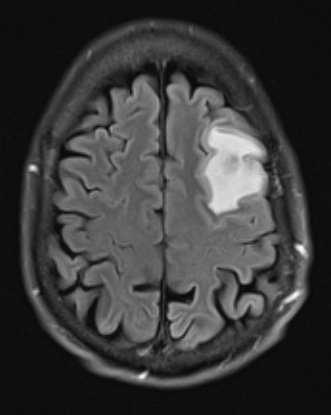

Case 5 History ---- The patient is a 48yo male with no significant past medical history who presented with blurry vision of the left eye and was found to have panuveitis and a left frontal brain lesion on imaging concerning for an abscess vs. metastatic disease. Operative procedure: Left frontal brain biopsy ---- 5A1 A focus of cerebritis with marked surrounding edema is seen in this FLAIR scan.